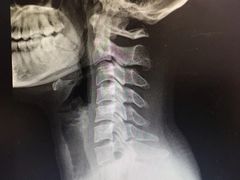

• -上海中医药大学附属曙光医院(东部)

贪捏惹花闯江湖 | 25-02-06